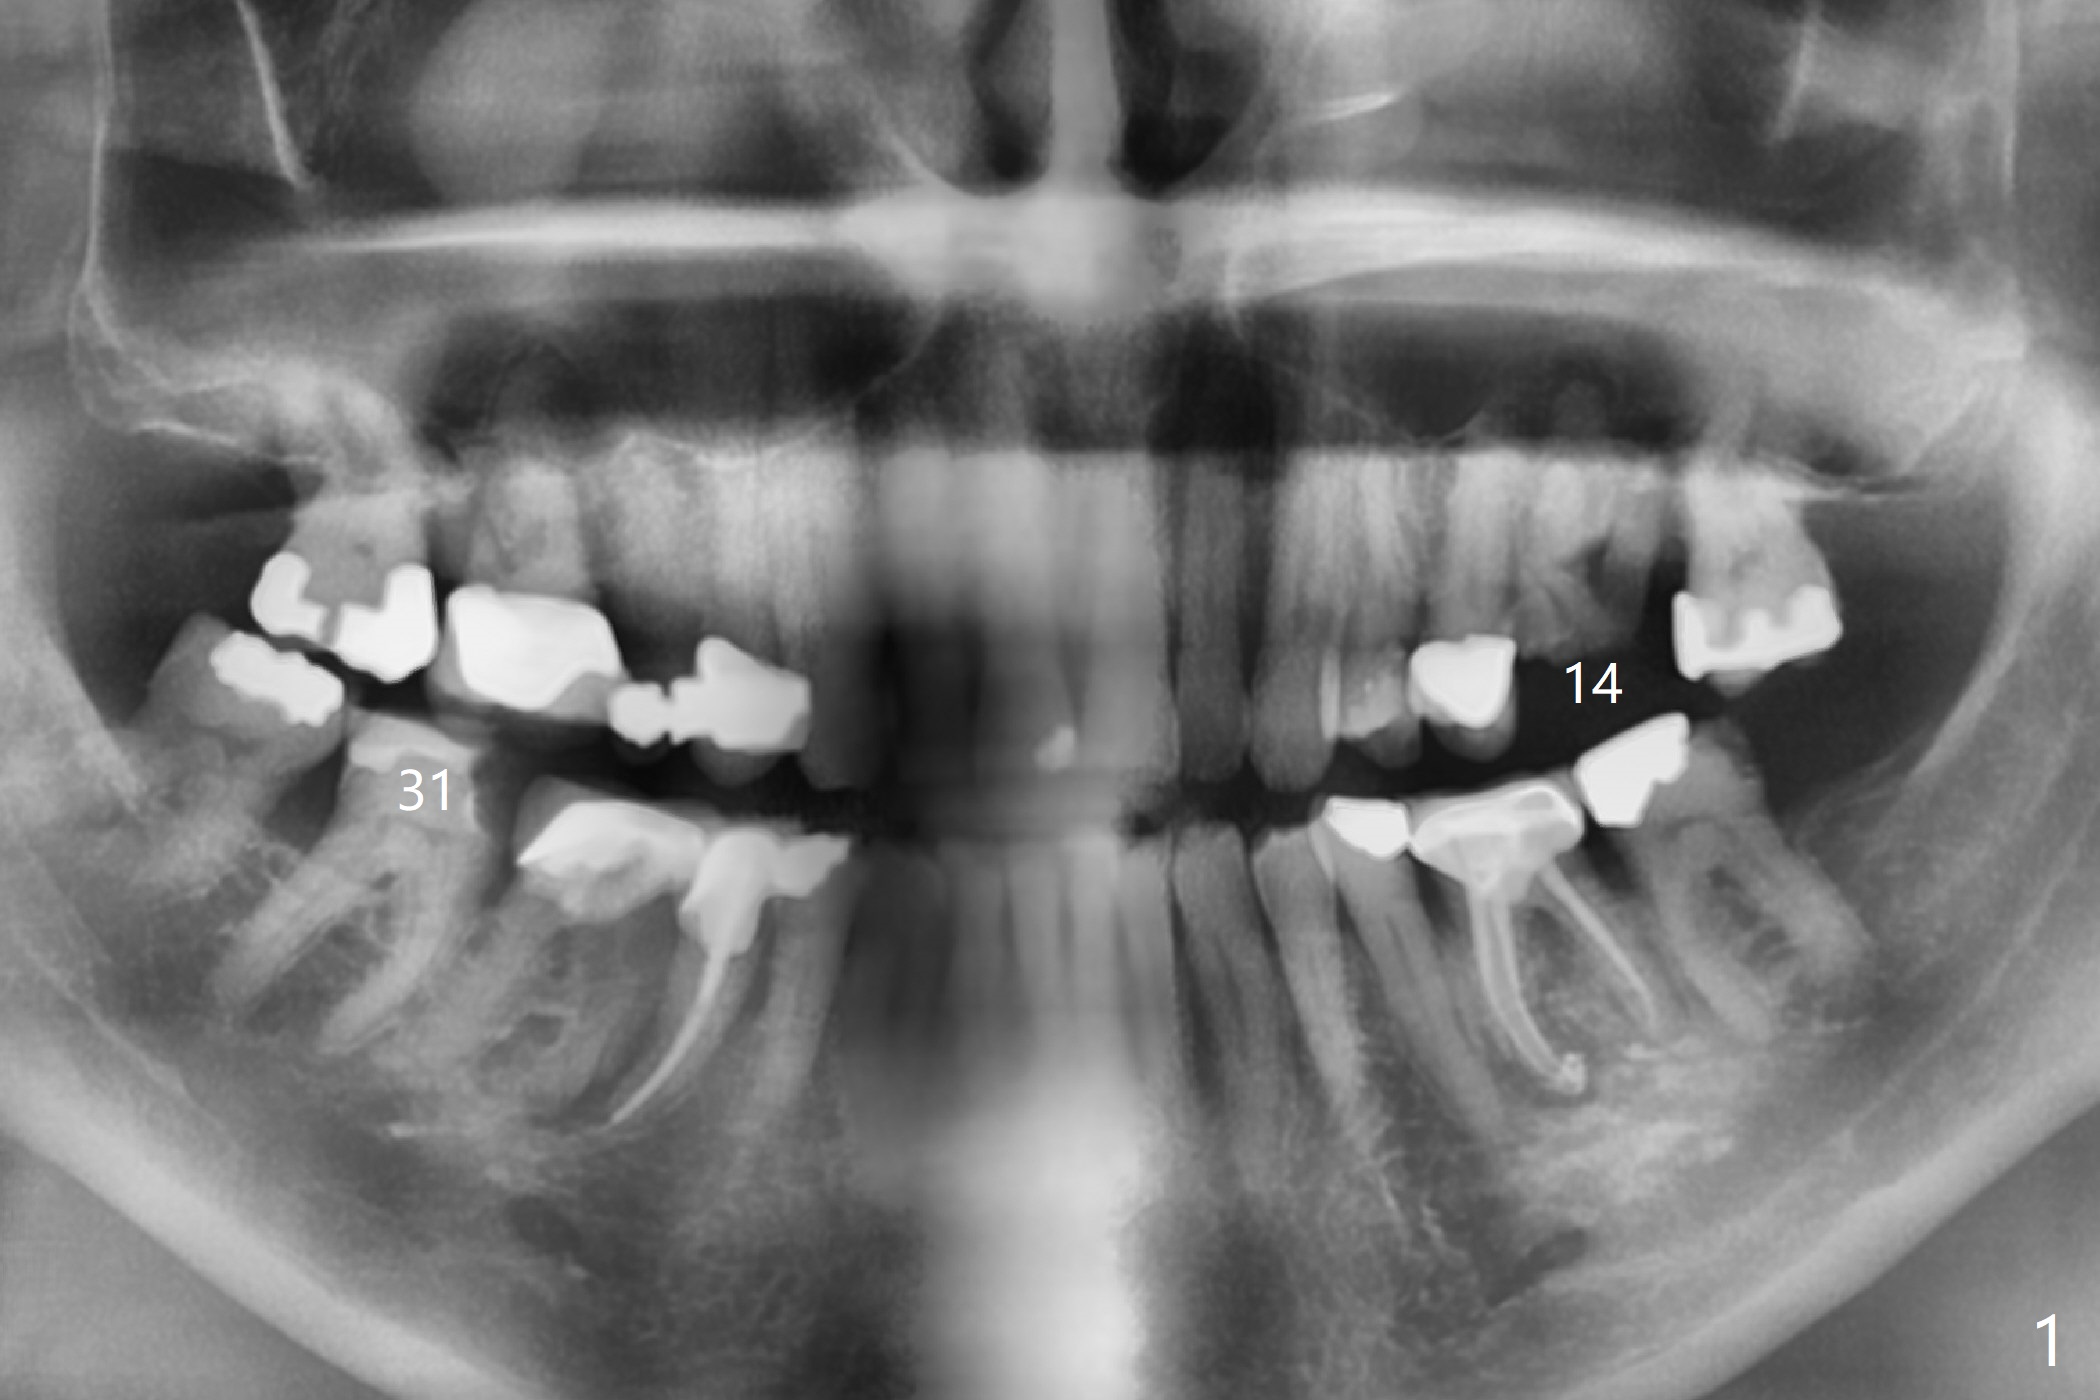

A 86-year-old man presents to clinic with chief complaint of irritating chipped tooth lower right (Fig.1 #31). Composite is placed on the condition that he should return for #14 residual root treatment (Fig.2). Since there is large periapical radiolucency and short bone height (~6 mm), should the tooth be extracted for immediate sinus lift and delayed implant or immediate implant (Fig.3)?